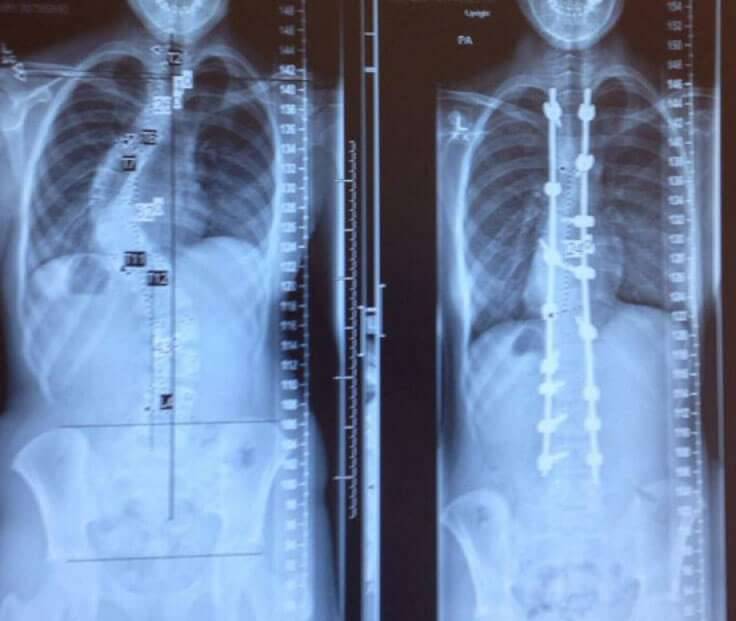

▼脊柱侧弯病人治疗前后的X光对比图。